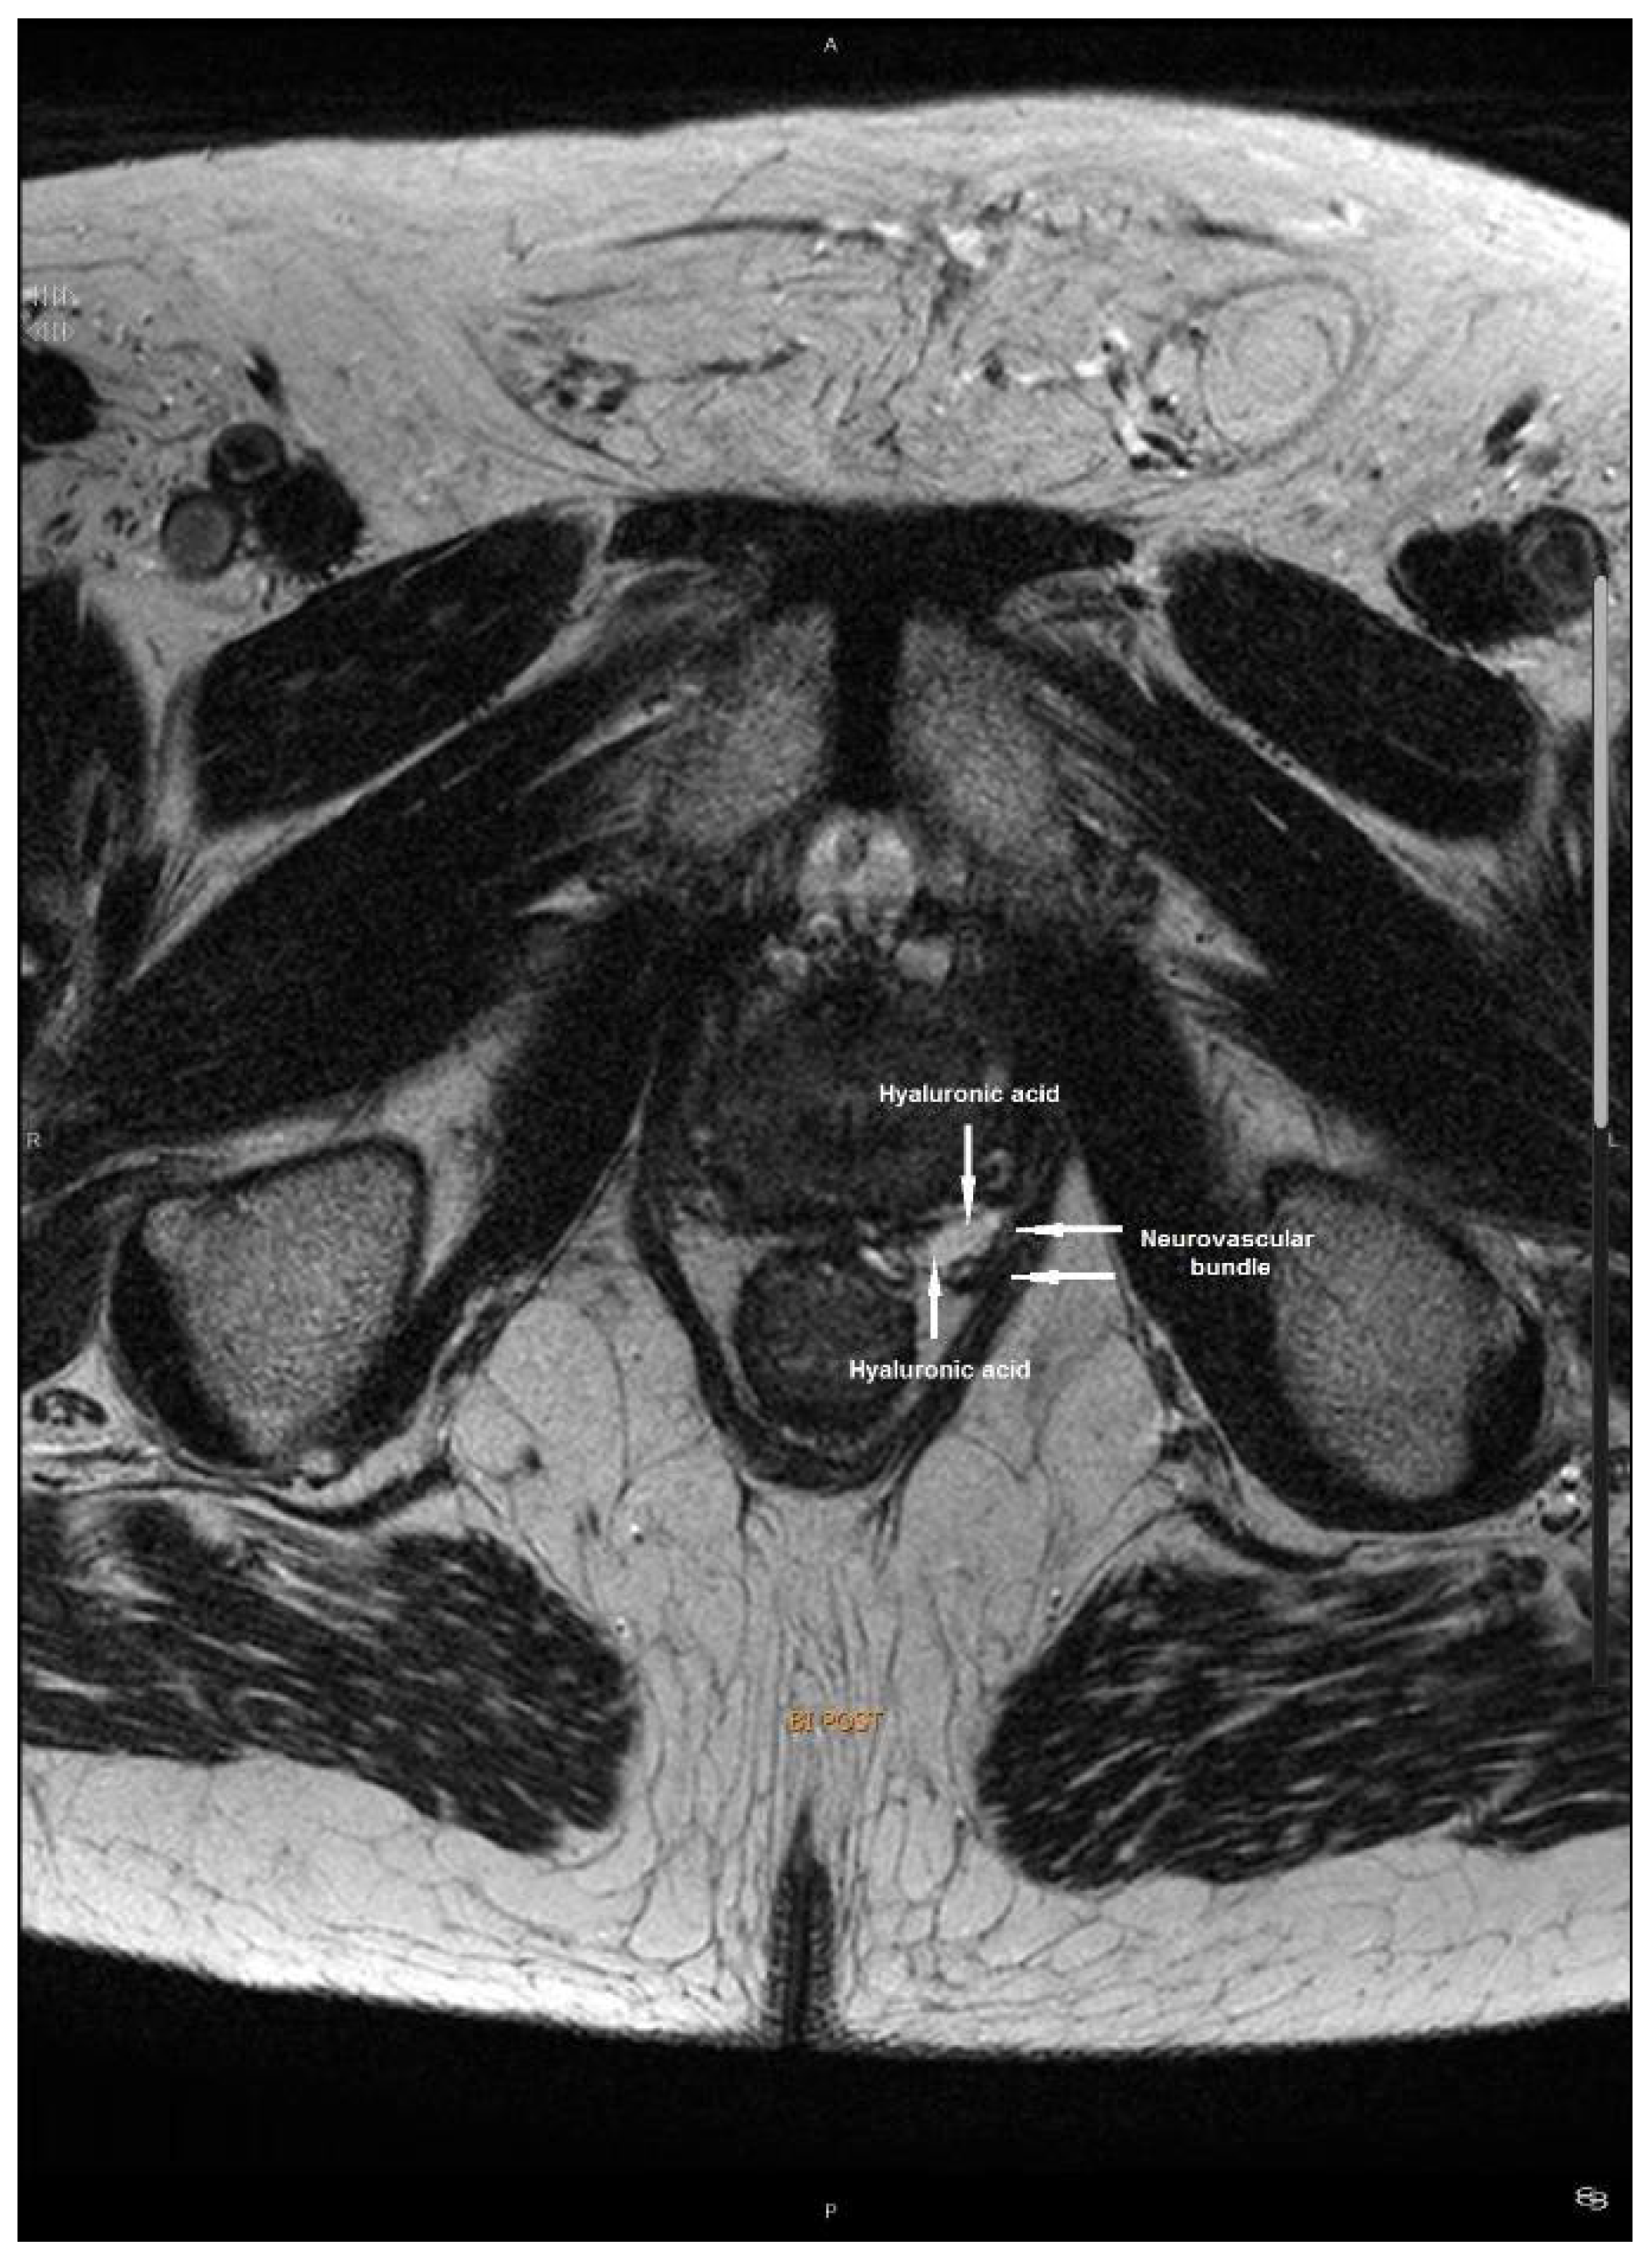

Intraoperative Neurovascular Bundle Preservation with Hyaluronic Acid during Radical Brachytherapy for Localized Prostate Cancer: Technique and MicroMosfet In Vivo Dosimetry

2.2. Technique of Hyaluronic Acid Injection